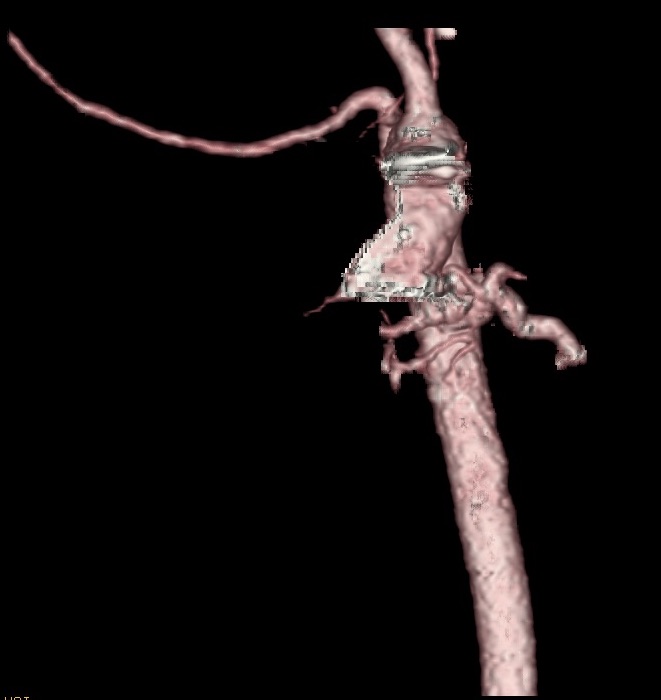

Along the proximal descending aorta, there was a large collateral originating from the left anterior aspect of the descending aorta, which gave rise to vessels that extended to the left lower lung (Figure 2). There were small branches that extended to the left upper lung as well as the right upper lung. There were tortuous branches that coalesced with the right main pulmonary artery branch. There was severe narrowing of the origin of the left main branch pulmonary artery.

Figure 2. CT arteriogram showing the presence of major collateral arteries branching from both the distal ascending and proximal descending aorta.